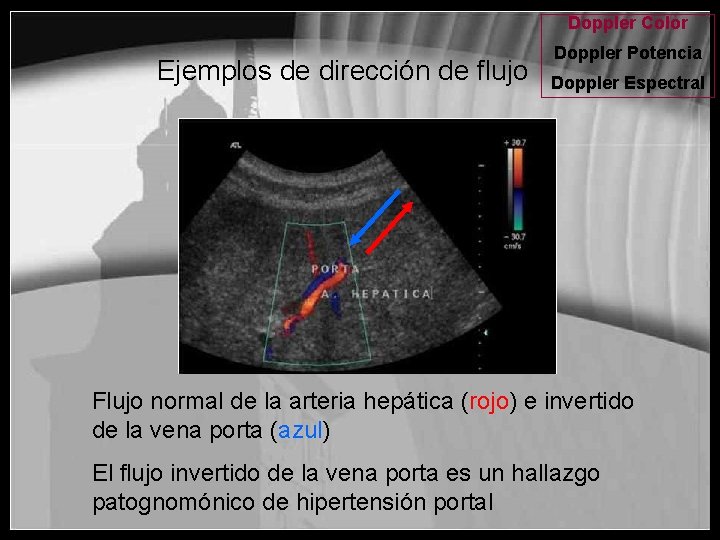

Doppler Color Ejemplos de dirección de flujo Doppler Potencia Doppler Espectral Flujo normal de la arteria hepática (rojo) e invertido de la vena porta (azul) El flujo invertido de la vena porta es un hallazgo patognomónico de hipertensión portal